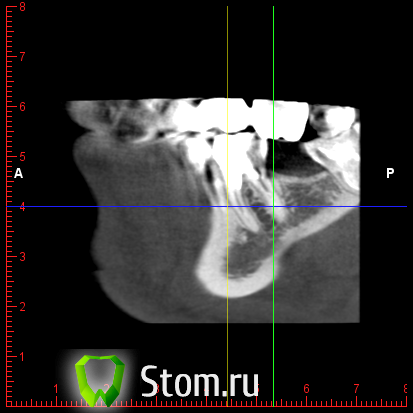

y2006 Опубликовано 3 мая, 2012 Автор Поделиться Опубликовано 3 мая, 2012 (изменено) прошу проконсультировать по поводу зуба 46. вопрос стоит в лечении и протезировании коронкой или удалении и заменой имплантом, правда ли что есть показания к удалению - перфорация корня? файлы для Romexis_Viewer по ссылке: (чуть позже)к сожалению не знаю как по другому выложить Изменено 3 мая, 2012 пользователем y2006 Ссылка на комментарий

y2006 Опубликовано 3 мая, 2012 Автор Поделиться Опубликовано 3 мая, 2012 снимок Ссылка на комментарий

y2006 Опубликовано 3 мая, 2012 Автор Поделиться Опубликовано 3 мая, 2012 (изменено) какие есть методы лечения? или есть необходимость в дополнительных проекциях? Изменено 3 мая, 2012 пользователем y2006 Ссылка на комментарий

y2006 Опубликовано 5 мая, 2012 Автор Поделиться Опубликовано 5 мая, 2012 (изменено) КТ IMAGES.rar46 зуб Изменено 5 мая, 2012 пользователем y2006 Ссылка на комментарий